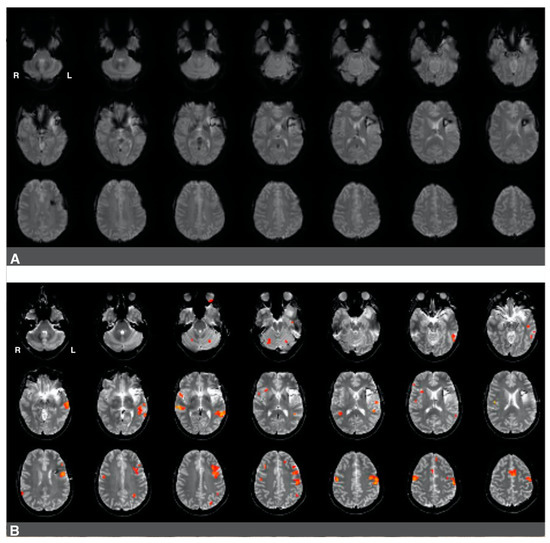

3.2. The Impact of Brain Surgery on Active Voxel Counts and Language Laterality